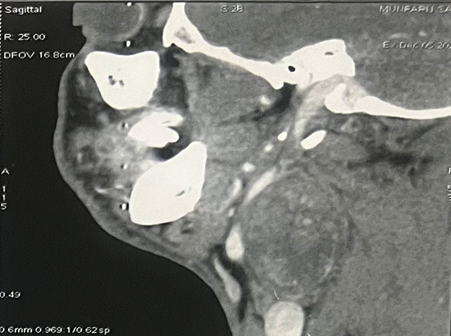

On the cervical CT scan, a voluminous mass well

limited to the right side of the cervix with carotid and jugular vascular

contact, the site of some calcification without contrast in arterial washout or

typical intercarotid topography, suggesting a glomus origin. (Figure 1).

Figure 1: CT imaging of a vagal schwannoma (red arrow) on the right

cervical side: (A) sagittal (B) axial and coronal (C) view.